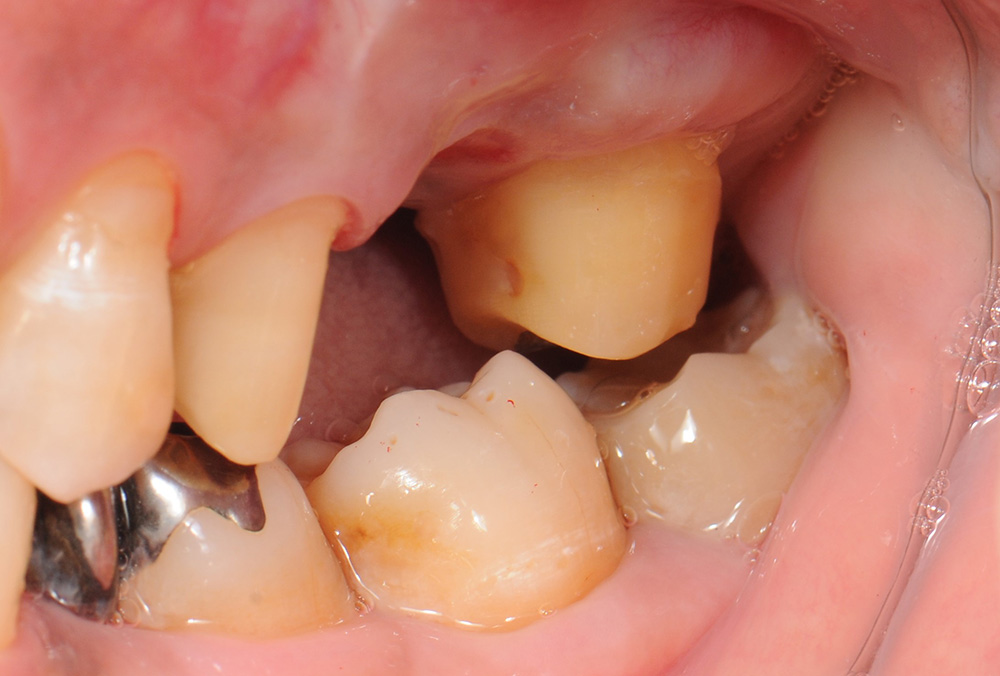

case2 症例(セラミッククラウン前歯)

治療前

| 費用(税込み) | 154,000円 |

|---|---|

| メリット・デメリット | デメリット 歯質を削合する必要がある |

| 治療回数 | 4-6回(根管治療は別) |

| 主訴 | 変色が気になる |